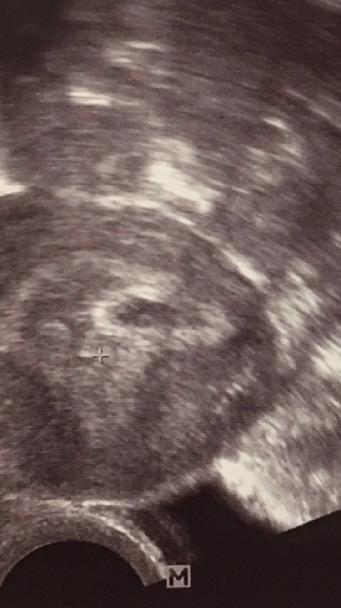

Holky mam strach a obavy , na ultrazvuku je videt genetacni vacek a kdyz se na to zblizka podivate myslite ze je naznak toho zlutkoveho vacku s polem takovy ty dve kolecka co je ve vacku myslite ze by to mohlo neco byt a za tyden uz srdicko ?na internetu jsem cetla ze uvnitr vacku by melo byt neco jako prstynek . Mnohokrat dekuji